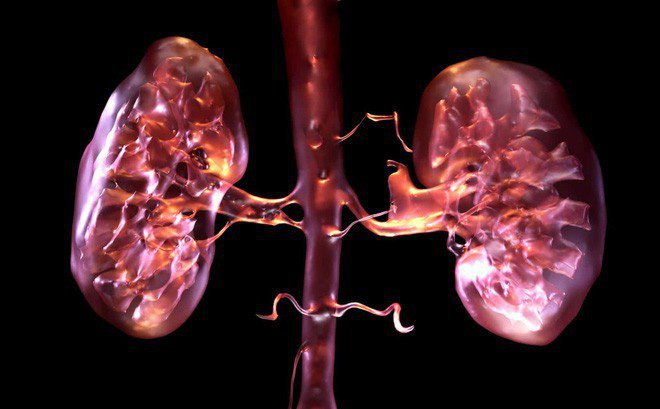

Quả thận có vai trò và ý nghĩa rất quan trọng đối với sự sống, giúp đào thải các chất cặn bã và chất độc ra khỏi cơ thể con người. Nếu thận khỏe, sẽ giúp con người bài tiết được nhiều chất thải ra khỏi cơ thể và ngược lại, nếu thận không làm tốt nhiệm vụ của mình, các chất cặn bã sẽ không đào thải được mà đọng lại cơ thể.

Nếu bị suy thận, chức năng bài tiết chất thải của cơ thể sau quá trình chuyển hóa không được thực hiện. Đặc biệt là suy thận mạn, các chức năng khác của thận bị suy giảm nghiêm trọng như điều hòa dịch, điện giải, toan kiềm, kích thích tạo máu, tổng hợp vitamin D đều bị rối loạn, có thể ảnh hưởng tới sự sống. Do đó, việc phát hiện sớm suy thận vô cùng quan trọng để có thể ngăn chặn các nguy cơ biến chứng ảnh hưởng nặng nề tới sức khỏe, tính mạng.

Trong cơ thể người có một loại protein trong gia đình các FABP có trọng lượng phân tử 14 kDa, khu trú chủ yếu ở các tế bào ống lượn gần của thận, tế bào gan, ruột… Khi ống lượn gần bị thiếu máu cục bộ hoặc thiếu oxy, thì mức L-FABP tăng cao, đặc biệt ở nước tiểu. Đo được hàm lượng L-FABP tăng cao cho phép bác sĩ chẩn đoán mức độ tổn thương thận, chẩn đoán sớm bệnh thận mạn có kèm theo rối loạn chức năng ống thận, xác định rối loạn vi tuần hoàn cấp ở ống thận. Đây là một dấu ấn sinh học mới phản ánh tình trạng nghiêm trọng của ống lượn trước khi có các dấu hiệu trên mô từ đó, bác sĩ có thể kịp thời điều trị.